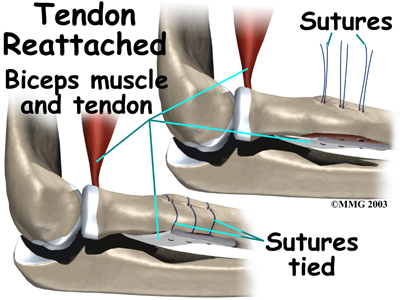

The tendon is passed between the radius and ulna, exiting through the second incision that was made on the back of the forearm. The sutures are threaded into the three holes that were drilled into the rim of the radial tuberosity. The surgeon ties the sutures, securing the . When the surgeon is satisfied with the repair, the skin incisions are closed, and the elbow is placed either in a cast or a range-of-motion brace.